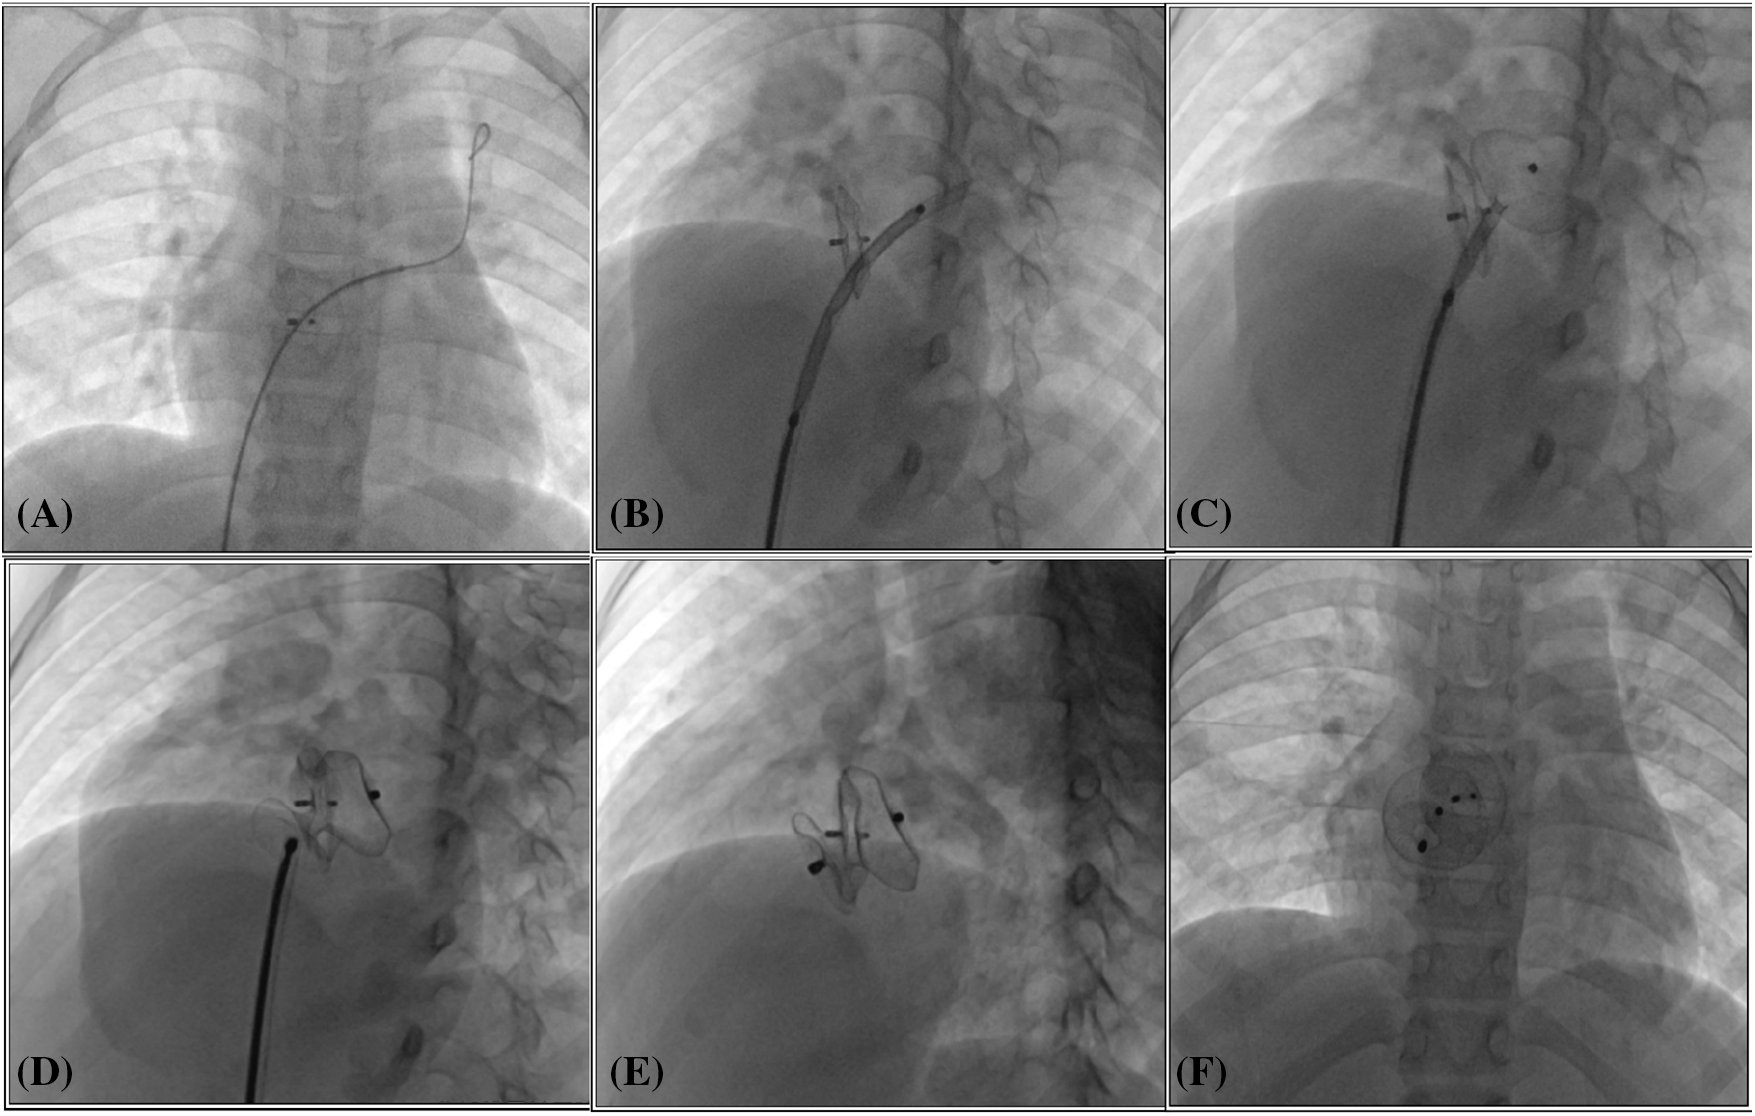

In this study, the TCC procedures were conducted by two skilled doctors with over 10 years of experience in CHD interventional treatment. We used the Amplatzer Septal Occluder (ASO, Abbott Medical, MN, USA), the Second-generation Amplatzer Ductus Occluder (ADOII, Abbott Medical, MN, USA), and a domestically manufactured atrial/ventricular septal occluder (Shanghai Shape Memory Alloy Co., Ltd., Shanghai, China). The choice of occluder was informed by transthoracic echocardiography (TTE), and left ventricular angiography, with the occluder’s positioning confirmed through fluoroscopy and TTE. TCC procedures were performed under local or general anesthesia, guided by both fluoroscopy and TTE. Access was obtained via puncture of the right femoral vein and/or artery, with a vascular sheath placed in the inguinal region. Patients received routine intravenous heparin administration at a dosage of 80–100 IU/kg. Standard right heart catheterization was conducted on all patients, followed by the TCC procedure as detailed in previous literature [5]. An appropriately selected occluder, attached to its delivery cable, was introduced through the femoral venous route using a delivery sheath and was precisely deployed at the designated site. Simplified illustrations of the TCC procedures for IAS (Fig. 1) and IVS (Fig. 2) are provided to offer visual clarity on the techniques employed.

Figure 1: Transcatheter closure of residual shunt following atrial septal defect occlusion. (A) The catheter and guide wire were adeptly navigated through the previously implanted occluder, successfully reaching the left upper pulmonary vein; (B) The occluder, attached to its delivery cable, was meticulously advanced through the delivery sheath, ultimately arriving at the left atrium; (C, D) Sequentially, the left and right discs of the occluder were deployed, ensuring a secure fit; (E, F) Following the occlusion, the occluder’s form and placement were carefully assessed using fluoroscopic imaging in both left anterior oblique and lateral views to confirm optimal positioning and functionality

Among the cohort, five patients were identified with IAS: one had a post-TCC atrial septal defect (ASD) and four had post-surgical repair ASD. The former was an 8-year-old girl with ASD and pulmonary valve stenosis. Five years after balloon pulmonary angioplasty, and transcatheter ASD closure, an 8 mm interatrial shunt was discovered via TTE. To address this, an additional 16 mm ASD occluder was effectively deployed, resulting in a complete obstruction of the shunt with no residual blood flow (Fig. 1).